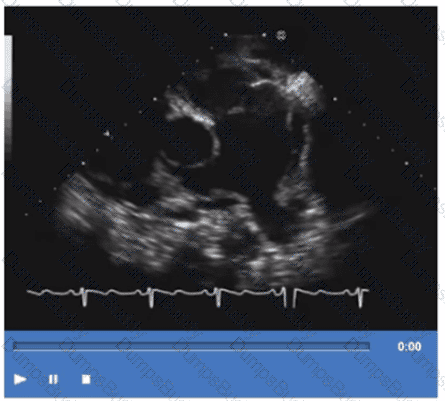

Which type of mass is typically attached to the fossa ovalis of the left atrium?